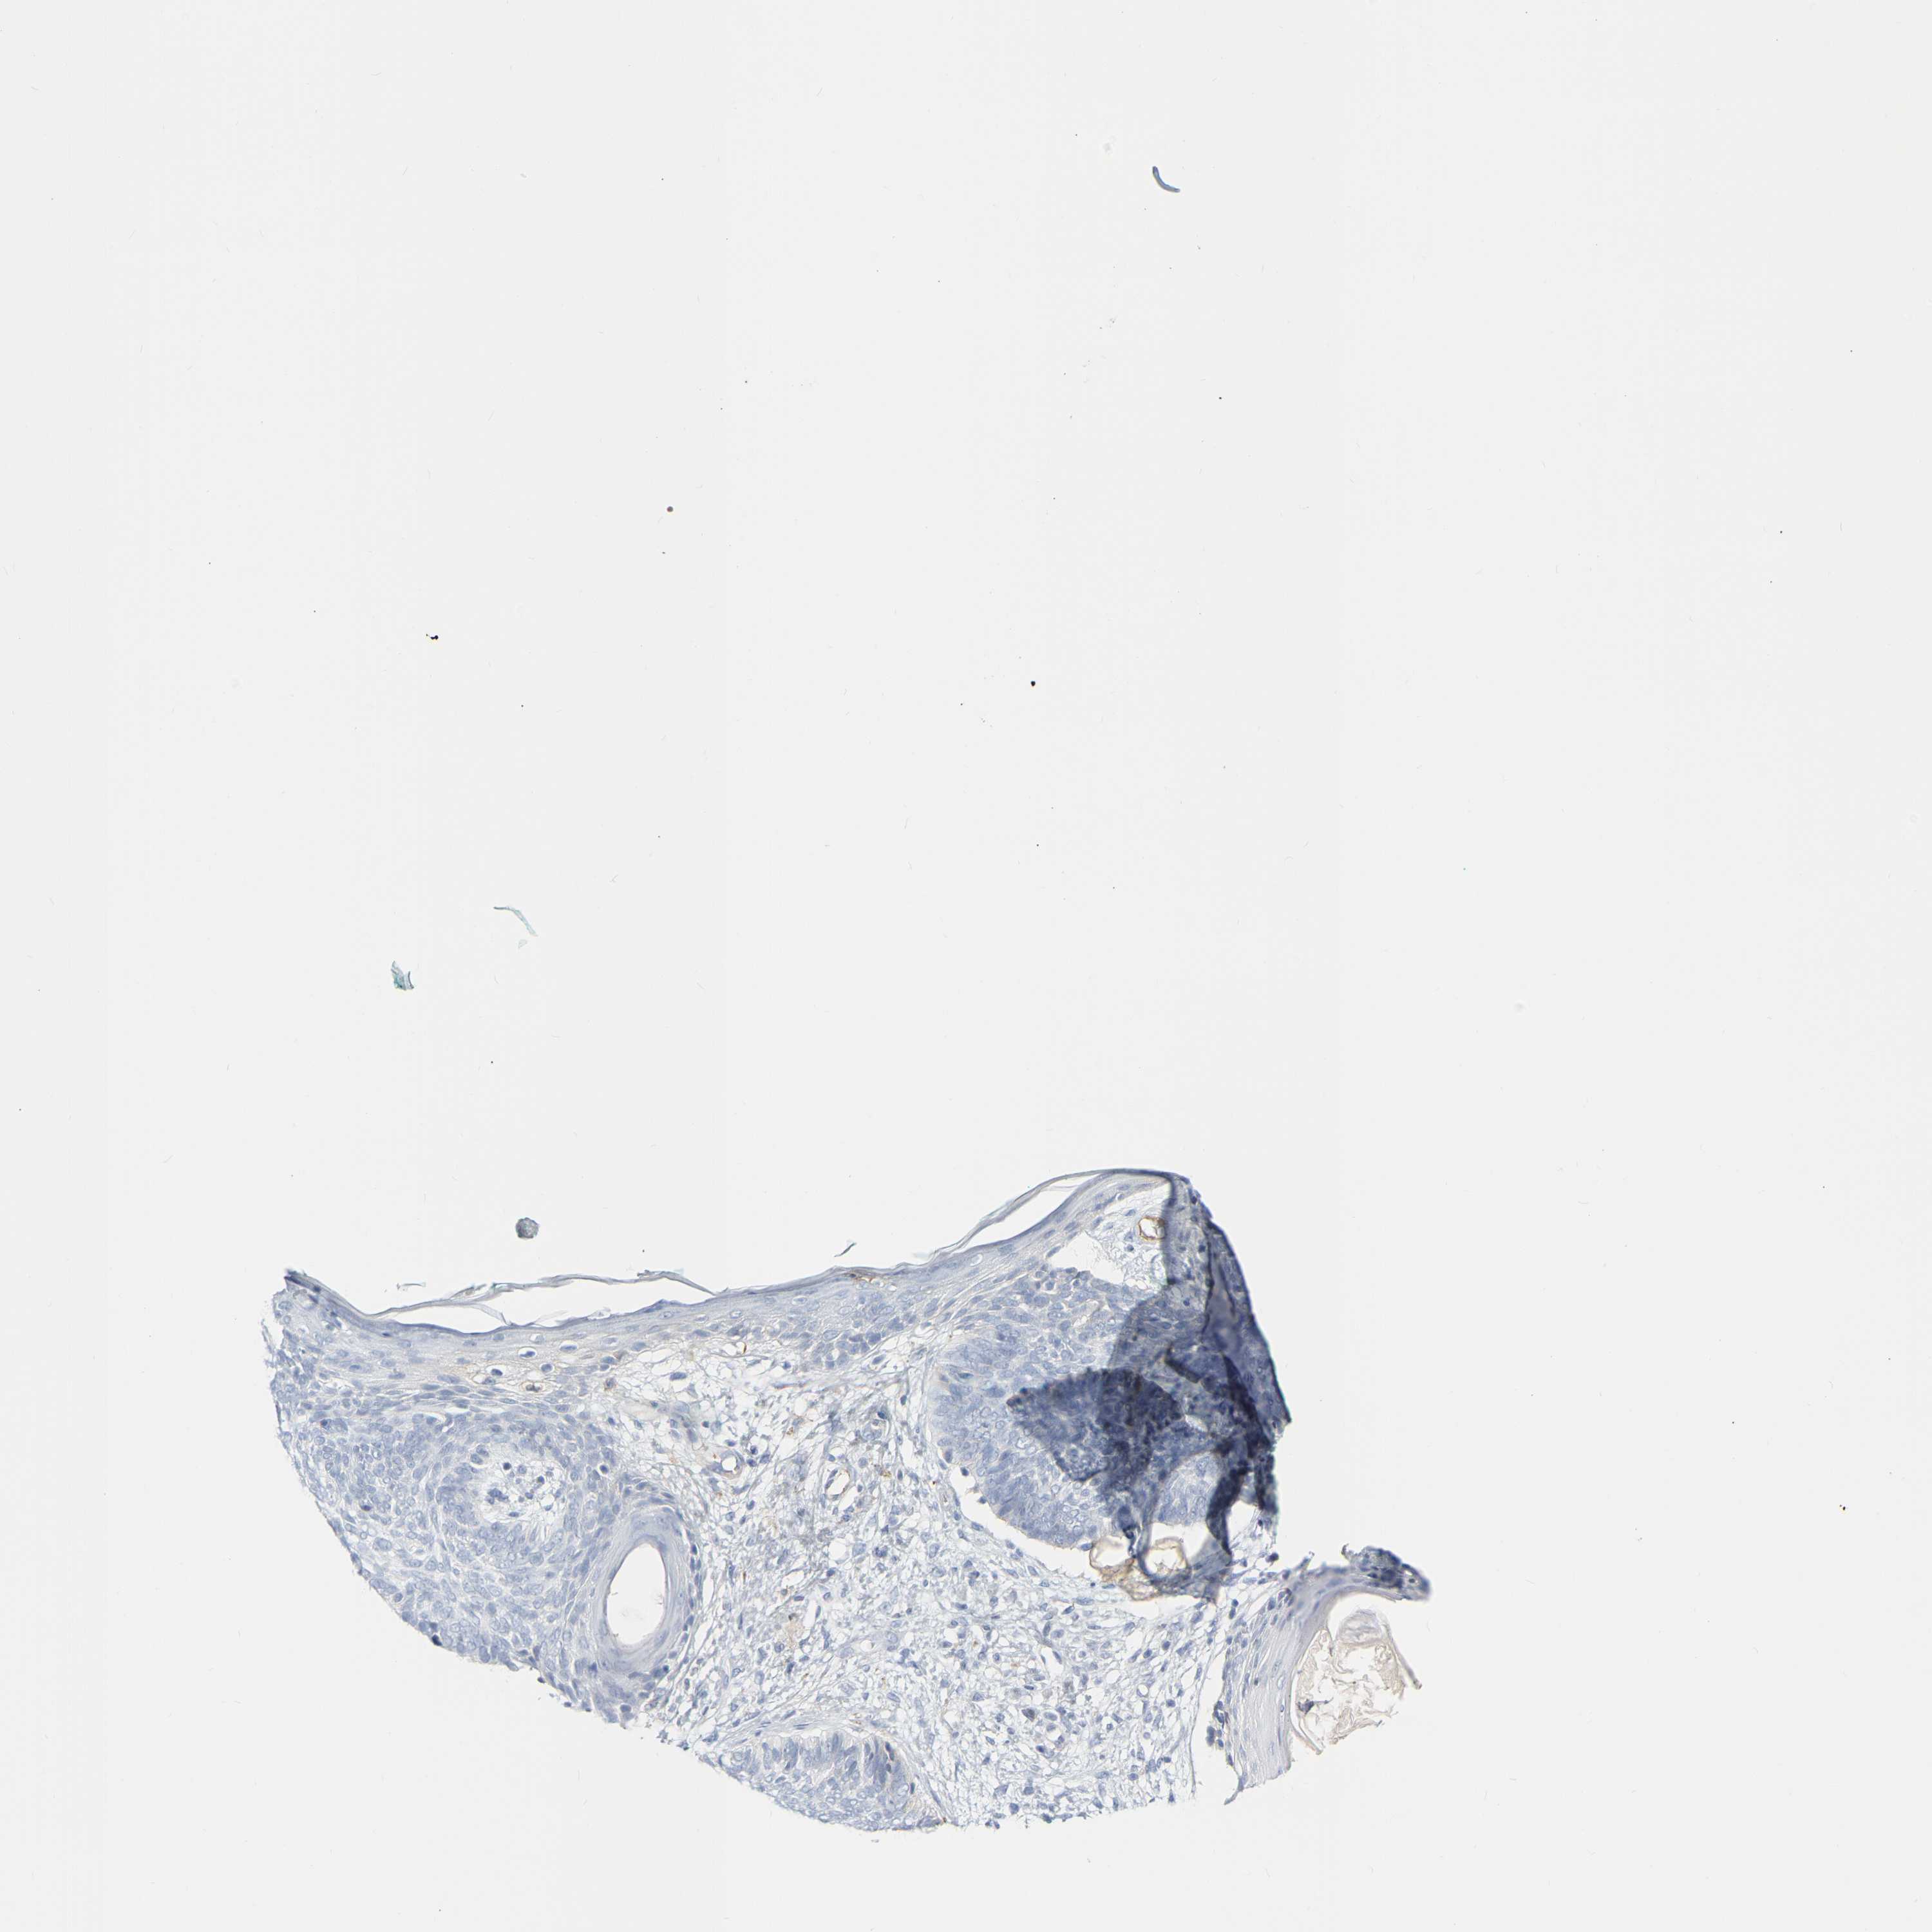

SKIN CANCER - Protein expressioni

A mouse-over function shows sample information and annotation data. Click on an image to view it in a full screen mode. Samples can be filtered based on level of antibody staining by selecting one or several of the following categories: high, medium, low and not detected. The assay and annotation is described here.

Each image is clickable and will lead to virtual microscopy that enables deeper exploration of all samples and also displays staining intensity scores, fraction scores and subcellular localization as well as patient and tissue information for each sample.

Antibody HPA018122

Basal cell carcinoma